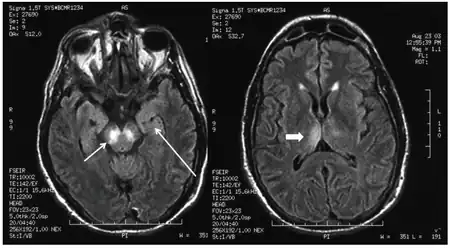

A stroke is an interruption of the blood supply to the brain. Approximately every 40 seconds, someone in the US has a stroke.[7] This can happen when a blood vessel is blocked by a blood clot or when a blood vessel ruptures, causing blood to leak to the brain. If the brain cannot get enough oxygen and blood, brain cells can die, leading to permanent damage.